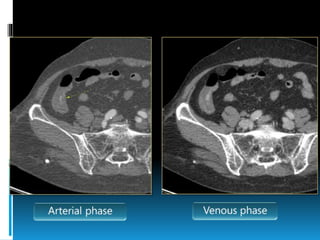

Multidetector row CT (MDCT)

 Show contrast

extravasation into any

portion of the

gastrointestinal tract

 Detects bleeding rates as

low as 0.3 to 0.5 cc per

minute

 The average yield of MDCT

for lower GI bleed Is 60%,

with yields ranging from

25% to 95%.

 Lack of therapeutic

capability is a major

limitation

 Useful in guiding further

angioembolisation